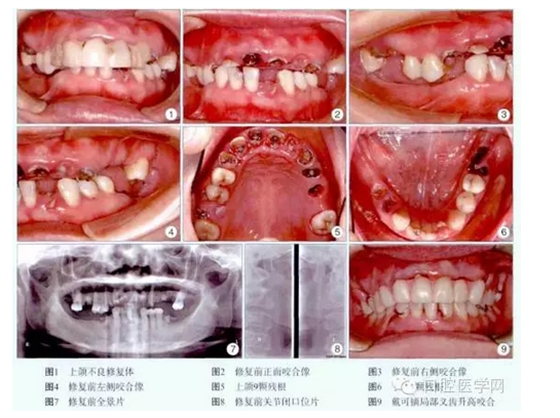

檢查:上前牙樹脂固定修復(fù),松動。11、12、13、16、21、22、23、24、25、32、36、44、45殘根,叩痛(+),1度松動。26、31、37、46、47缺失,牙槽嵴較豐滿。14、15、17、27、33、34、35、41、42、43齲齒,叩痛(-),松動(-)。正中牙合位無牙合接觸,咬合垂直距離降低,息止牙合間隙6mm,張口度正常,無顳下頜關(guān)節(jié)彈響及觸痛,牙石I度,齦緣紅腫(圖1~6)。全景片示所有殘根根尖有透光區(qū),多數(shù)牙牙槽骨水平吸收約根長的1/4~1/3,可利用牙槽骨高度:16為12.5mm,24為14.9mm,26為11.0mm(圖7)。關(guān)節(jié)片未見明顯異常(圖8)。

診斷:①上頜不良修復(fù)體,②上下牙列缺損,③慢性牙周炎,④14、15、17、27、33、34、35、41、42、43齲齒,⑤11、12、13、16、21、22、23、24、25、32、36、44、45殘根。治療過程:術(shù)前拍全景片,關(guān)節(jié)片,取研究模,照數(shù)碼像,簽署知情同意書。潔牙,拔除11、16、22、24、25、36、44、45殘根。14、15、17、27、33、34、35、41、42、43用FiltekZ350納米樹脂(3M公司,美國)充填。膠托可摘局部義齒升高咬合4mm,重新建立新的頜位關(guān)系(圖9)。